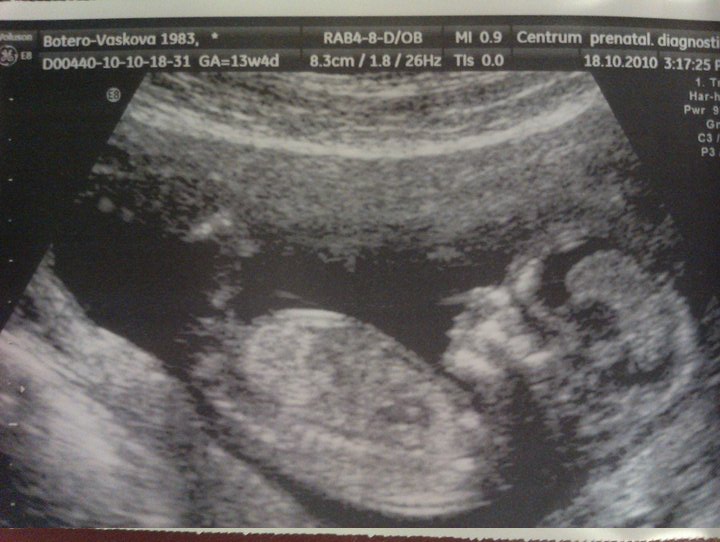

Baby in its beauty in 13 weeks of my pregnancy